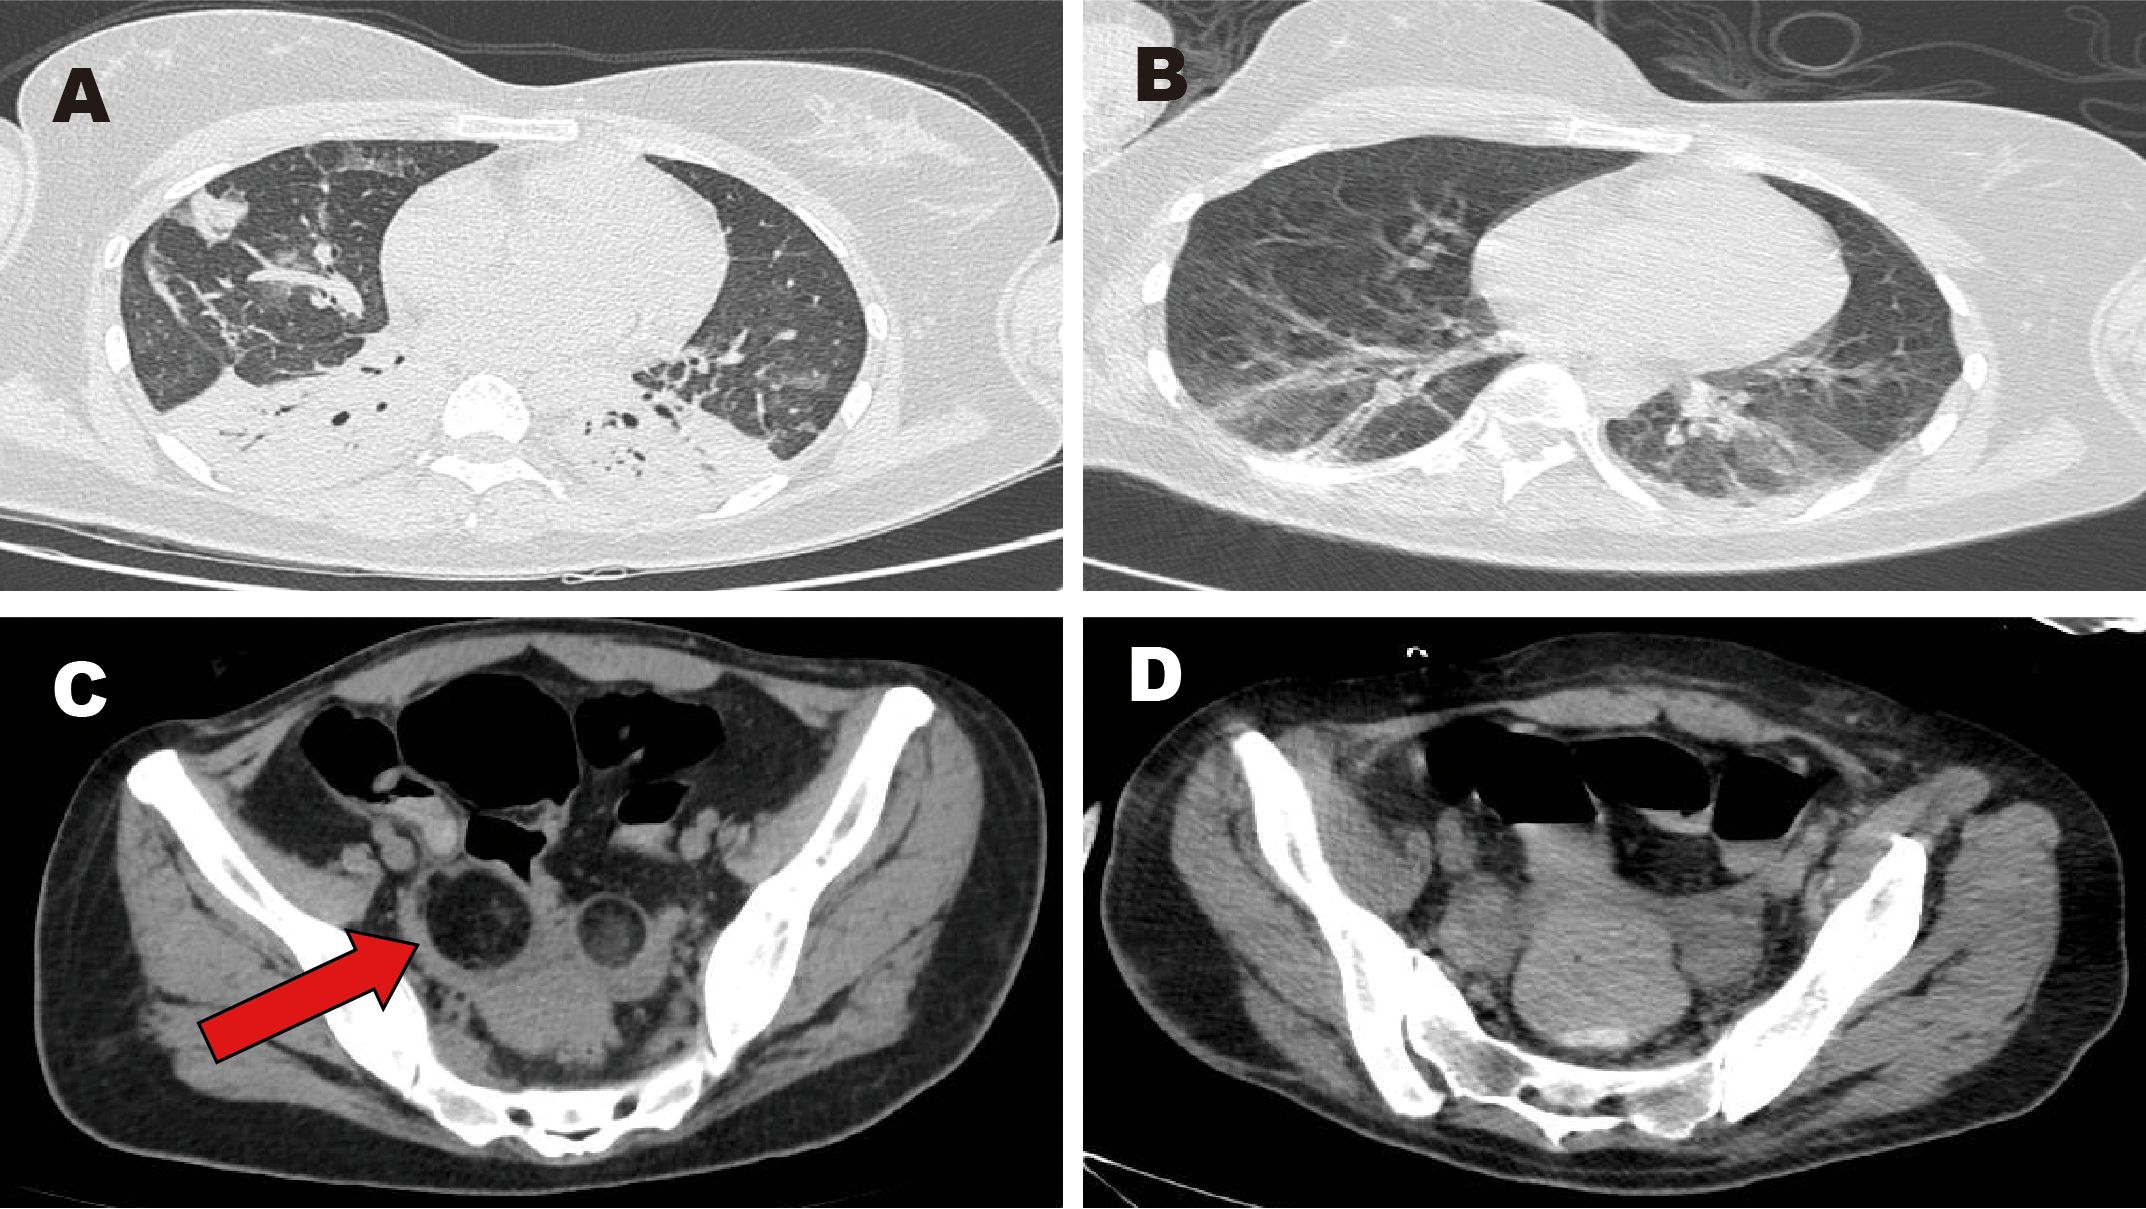

Upon admission to our hospital, she was intubated and sedated for pain management. Piperacillin-tazobactam (4.5 g every 8 hours for 4 days) was initially administered to manage the pulmonary infection (Figure 1A: inflammation in both lower lungs with partial atelectasis). On days 1–4, bronchoalveolar lavage fluid analysis identified carbapenem-resistant Acinetobacter baumannii. Based on antimicrobial susceptibility testing, the antibiotic regimen was adjusted to cefoperazone-sulbactam (3 g every 8 hours for 1 month). However, the patient continued to experience recurrent fevers, with temperatures fluctuating above 38°C; she expectorated a large volume of yellow purulent sputum. Repeated laboratory tests indicated worsening infection markers and deteriorating arterial blood gas parameters. On days 1–8, colistimethate sodium (500,000 units every 12 hours for 19 days) was added to the antimicrobial regimen. Due to prolonged intubation, severe pulmonary infection, excessive oral secretions, and a weak cough reflex, percutaneous tracheostomy was performed on day 9. Anti-infective therapy continued concurrently. During hospitalization, serial bronchoalveolar lavage fluid tests showed a gradual decline in A. baumannii, as well as detection of small amounts of Stenotrophomonas maltophilia and Pseudomonas aeruginosa. Infection markers (Table 1) and chest computed tomography (CT) findings improved; the patient exhibited only occasional low-grade fever. On days 1–27, tigecycline (50 mg every 12 hours for 8 days) was administered as monotherapy. Body temperature and laboratory indices then normalized. Subsequently, an antibiotic de-escalation strategy was implemented using cefoperazone-sulbactam (2 g every 8 hours for 2 days).

Figure 1. Images of chest and pelvic computed tomography (CT). (A, C) CT scans obtained before surgery. (B, D) CT scans obtained after surgery. Red arrow: mixed-density lesion in the right adnexa.

The patient’s main manifestations of epilepsy included impaired consciousness and recurrent convulsions involving the lips, face, and limbs. Glucocorticoids were administered in combination with multiple antiepileptic and sedative agents, including levetiracetam (particularly effective for partial seizures and primary generalized tonic-clonic seizures), valproate (effective for generalized and partial seizures), phenobarbital (suitable for status epilepticus), lacosamide (primarily used for monotherapy or adjunctive treatment of partial-onset seizures), midazolam, and dexmedetomidine. However, seizure control remained inadequate. EEG: Severely abnormal, with continuous, diffuse, high- to very-high-amplitude delta activity predominating across all leads and interspersed with a moderate amount of beta activity. Abdominal CT showed mixed-density lesions in both adnexal regions, measuring approximately 5.0×4.8 cm on the right and 2.3×2.3 cm on the left, suggestive of teratomas (Figure 1C). After multidisciplinary consultation, the ovarian teratoma was identified as the likely trigger of autoimmune encephalitis. On January 25, 2024, the patient underwent laparoscopic bilateral ovarian teratoma resection under general anesthesia (Figure 2A). Intraoperative findings included teratomatous tissue containing fat and hair (Figure 2B). Postoperative hematoxylin and eosin staining confirmed the histopathological features of teratoma (Figure 2C). Postoperative abdominal CT (Figure 1D) confirmed the absence of teratomas, and chest CT (Figure 1B) showed significant resolution of inflammatory changes in both lower lung lobes. The postoperative EEG remained severely abnormal but showed clear improvement compared with the preoperative tracing. It displayed continuous diffuse moderate- to high-amplitude delta activity, scattered theta waves, and prominent beta activity. The frequency and severity of limb and facial convulsions were also reduced.